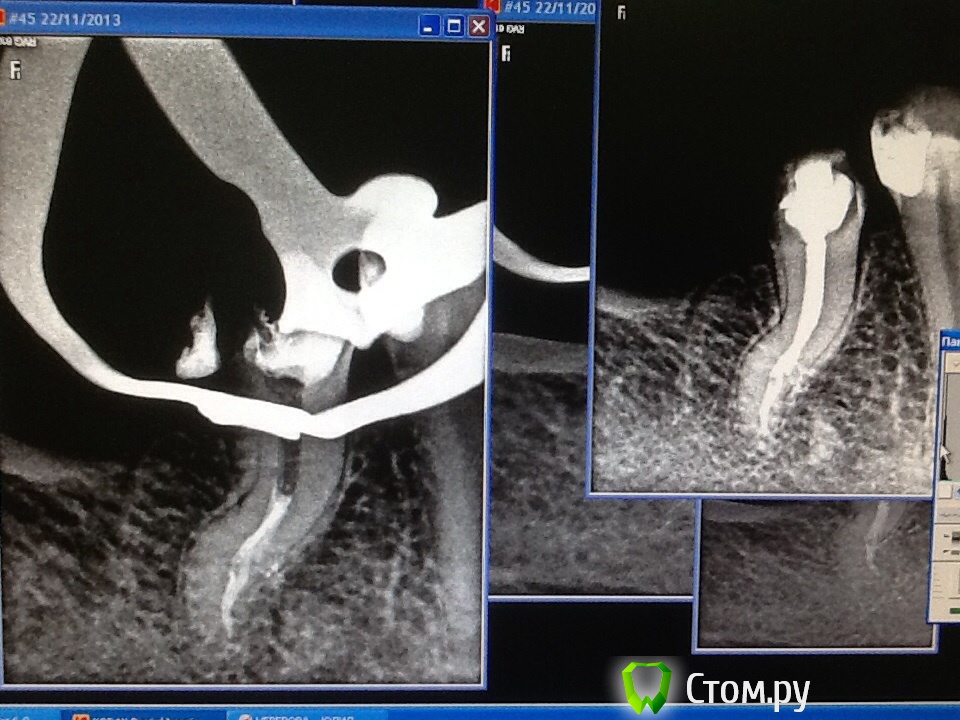

Л Ю С Я Опубликовано 25 ноября, 2013 Автор Поделиться Опубликовано 25 ноября, 2013 Спасибо всем за советы по поводу паковки сквирт. На фантомах попробовать не получилось- вон куча зубиков вторую неделю киснет в формалине - ну просто некогда, все пробую во рту. Действительно, плюется намного меньше.А вот этот зуп меня не порадовал. Как я не пыталась в бинокулярах разглядеть вход в третий канал, ничего не получилось- было много хлорки, эдта, спирт, не знаю вроде гутта затеклаА может силер? 6 Ссылка на комментарий

ger_berra Опубликовано 25 ноября, 2013 Поделиться Опубликовано 25 ноября, 2013 (изменено) Спасибо всем за советы по поводу паковки сквирт. На фантомах попробовать не получилось- вон куча зубиков вторую неделю киснет в формалине - ну просто некогда, все пробую во рту. Действительно, плюется намного меньше.image.jpgimage.jpgА вот этот зуп меня не порадовал. Как я не пыталась в бинокулярах разглядеть вход в третий канал, ничего не получилось- было много хлорки, эдта, спирт, не знаю вроде гутта затеклаimage.jpgА может силер?Люсь,последний снимок -бомба! Очень нравится!Помыли отменно.И,кмк,не важно,гутта там или силер. Изменено 25 ноября, 2013 пользователем ger_berra Ссылка на комментарий

Л Ю С Я Опубликовано 25 ноября, 2013 Автор Поделиться Опубликовано 25 ноября, 2013 Люсь,последний снимок -бомба! Очень нравится!Помыли отменно.И,кмк,не важно,гутта там или силер. Спасибо! Последнее время с нижними премолярами мне везет! Скажите, а с микриком реально где- то в средней трети канала увидеть вход в такое ответвление ? Ссылка на комментарий

M@estro Опубликовано 25 ноября, 2013 Поделиться Опубликовано 25 ноября, 2013 image.jpgА может силер? Супер ! Люся,5! Ссылка на комментарий